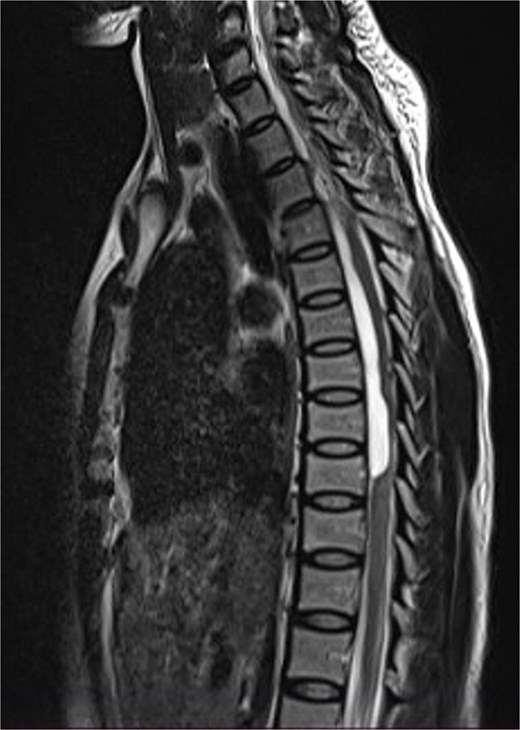

Thoracic and lumbosacral spine MRI showed an intradural-extramedullary cystic lesion, hypointense on T1 and hyperintense on T2-weighted images, extending from T5 to T9 vertebral levels with posterior displacement and flattening of the cord at the same levels (Fig. 5). There were multiple disc bulges at L3/L4, L4/L5, and L5/S1 with minimal thecal compression. A diagnosis of thoracic intradural AC was made.

Sagittal T2-weighted thoracic spine MRI images showing an anteriorly located intradural arachnoid cyst at T5–T9, posteriorly displacing and compressing the spinal cord.